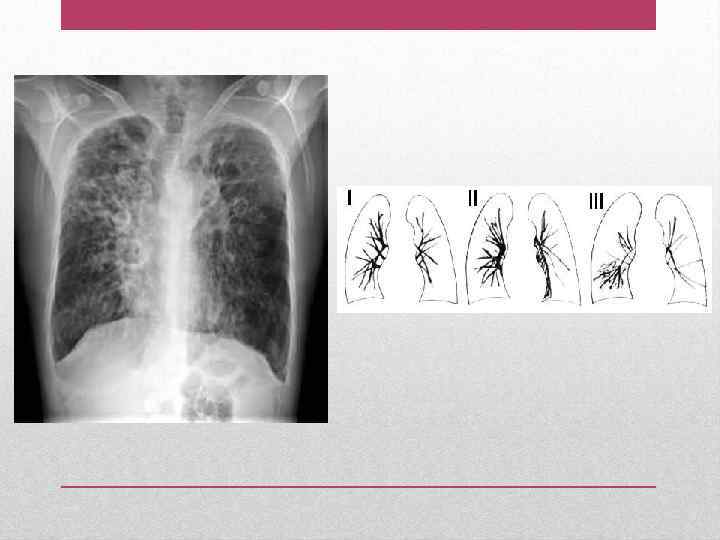

• Усиленный с деформацией легочный рисунок в нижних легочных полях, доходящий до периферических отделов легких, наличие ателектаза в нижних долях, средней доле, язычковых сегментах. • Ячеистый легочной рисунок в области нижних сегментов легких. • Тонкостенные кистоподобные просветления (полости) иногда с уровнем жидкости (при значительно выраженных мешотчато-кистозных бронхоэктазах в средней доле) • Уменьшение объема пораженных сегментов. Рентгенография органов грудной клетки

• I стадия: цилиндрические бронхоэктазы в пределах одного легочного сегмента. • II стадия: распространенное поражение (1 -2 доли), участки фиброза легочной ткани, в периоды обострения – фокусы пневмонии. Компьютерная томография легких